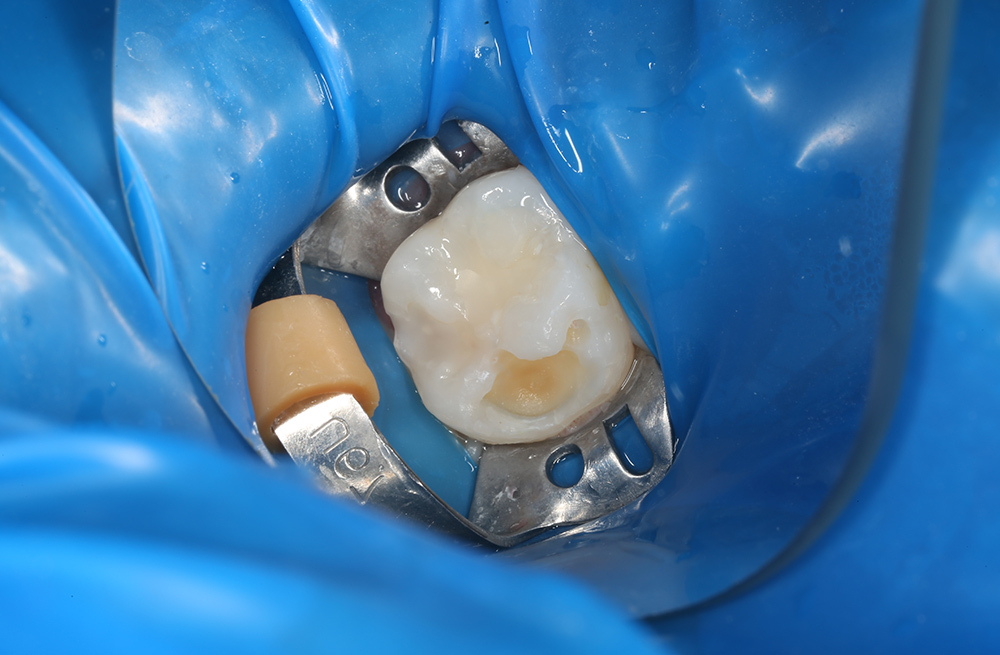

Лечение за один визит, где один зуб спасли коронкой, а соседний восстановили пломбой